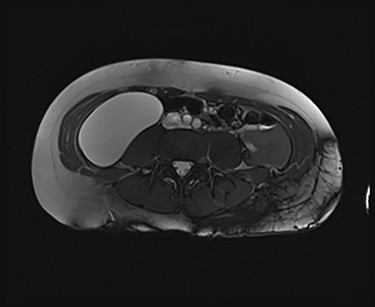

We present an extremely rare and isolated case of primary mixed serous and mucinous cystadenoma in a 49-year-old otherwise fit and healthy female patient. She was referred to our consultant with a history of discomfort on the right side of her abdomen for few years, which increased gradually with no other complains. The patient had further investigations conducted including computed tomography (CT) (Figs 1 and 2) that demonstrated the position and size of the lesion. The magnetic resonance imaging (MRI) revealed a large cystic lesion in the right retroperitoneal region shown in Figs 3 and 4. Her full blood count, inflammatory markers, urea and electrolytes and liver function tests were within the normal limit. Consequently, the patient had a laparoscopic resection of an isolated retroperitoneal cyst. At surgery, the cystic lesion seemed to be arising from mesentery and the lesion was dissected intact and completely excised. Histopathology revealed a benign mixed serous and mucinous cystadenoma as shown in Fig. 5. The patient was discharged from the hospital with no complications and fully recovered on follow-up review. Patient was discussed in a multidisciplinary team meeting and the recommendation was for no further management.